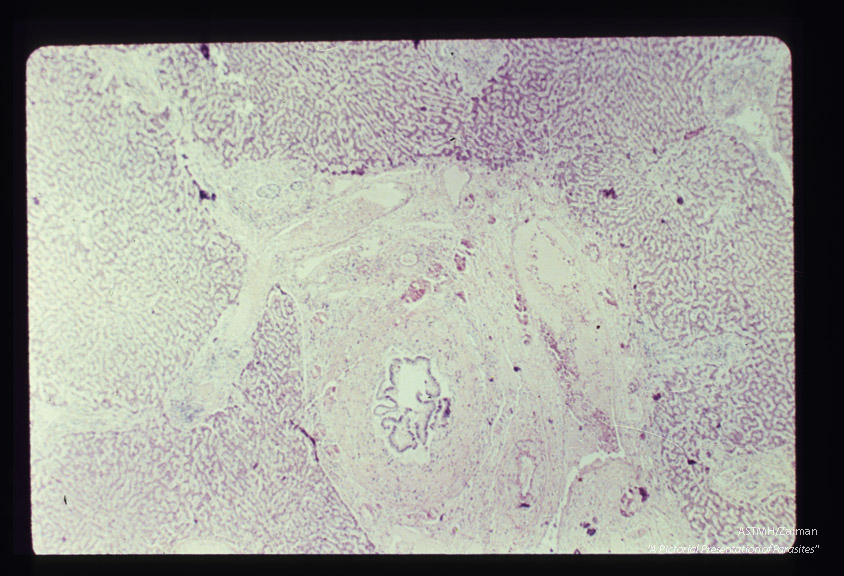

Human liver showing periportal fibrosis due to worms in biliary ducts.

Fasciola gigantica

Description: Human liver showing periportal fibrosis due to worms in biliary ducts.